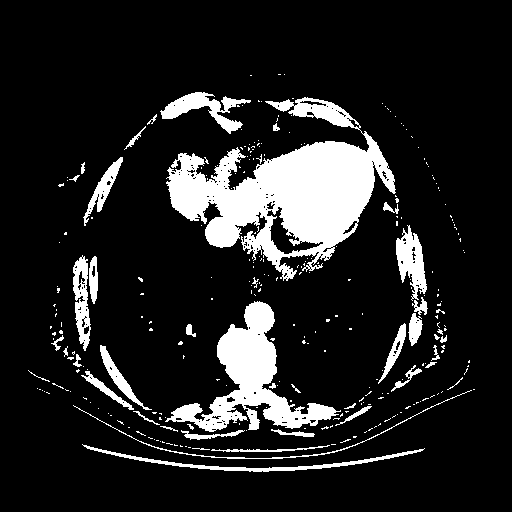

Original NATIVE CT scan (input)

Full window (WL 1023.5, WW 4095 β†’ Low βˆ’1024, High +3071)

Actual HU range: [-1024.0, 3071.0]

Lung window (WL -600, WW 1500 β†’ Low βˆ’1350, High +150)

Actual HU range: [-1350.0, 150.0]

Mediastinum window (WL 40, WW 400 β†’ Low βˆ’160, High +240)

Actual HU range: [-160.0, 240.0]